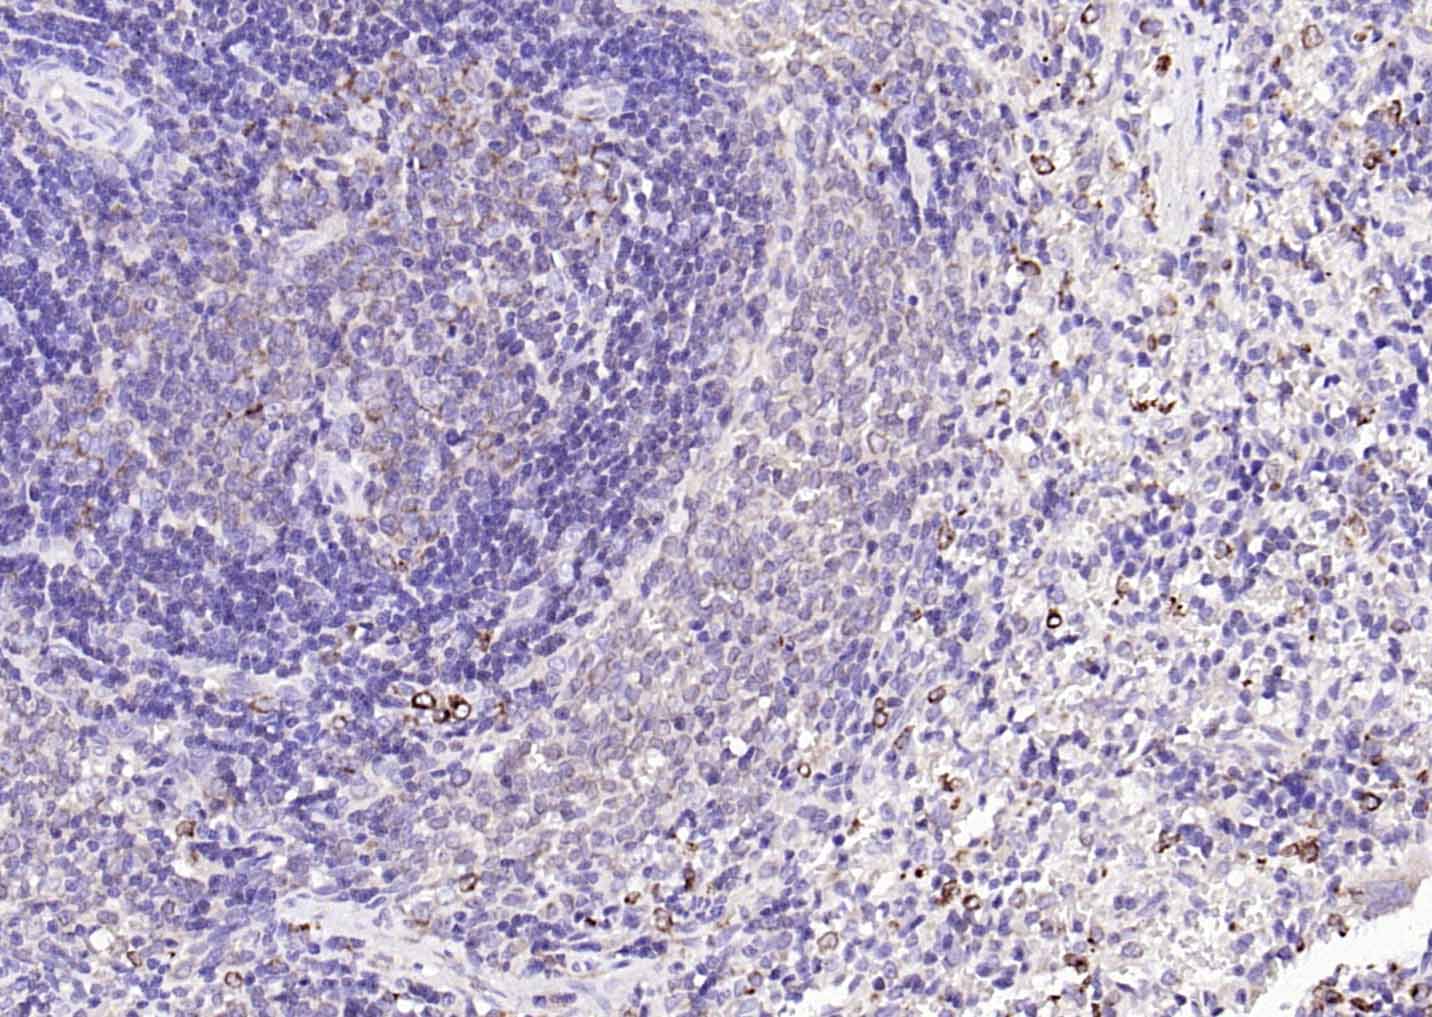

| 英文名称 | CD74 Rabbit pAb |

| 中文名称 | CD74抗体 |

| 产品应用 | IHC-P=1:100-500, IHC-F=1:100-500, IF=1:100-500, ELISA=1:5000-10000 Not yet tested in other applications. |

| 交叉反应 | Mouse |

| {IHC-P} | {1:100-500} |